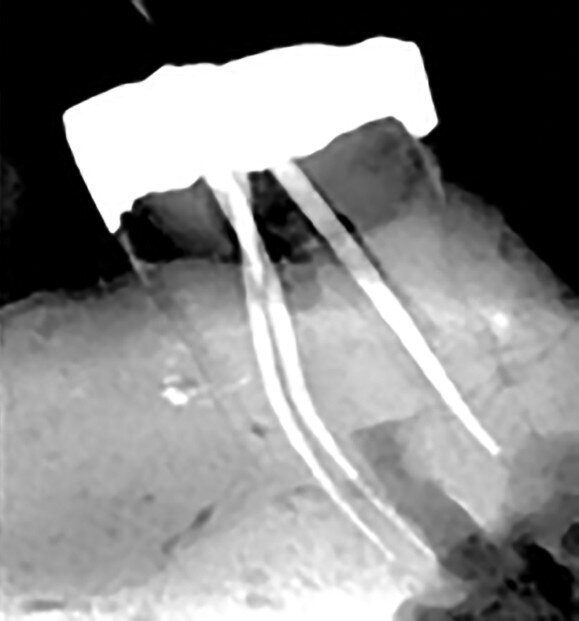

Figs. 12a–d : Depuis la gauche : Cas de l’auteur : dent

37 présentant une fracture radiculaire ; cette dent

montée dans un modèle en plâtre-pierre après extraction,

avec impression du guide de forage CTGEA

monté et du premier foret en place ; les deux

petits orifices d’accès préparés au moyen du guide

de forage ; et la radiographie postopératoire montrant

l’adaptation des cônes dans les canaux après leur négociation et leur mise en forme.